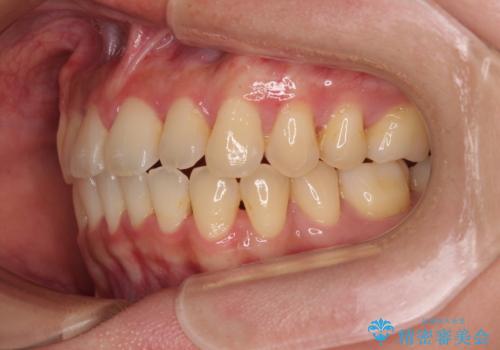

- 上下前歯のデコボコやクロスバイトを気にして来院された患者様です。

上顎歯列が下顎の歯列に対して狭小であり、一部下顎の奥歯が上顎よりも外側に位置している状態でした。